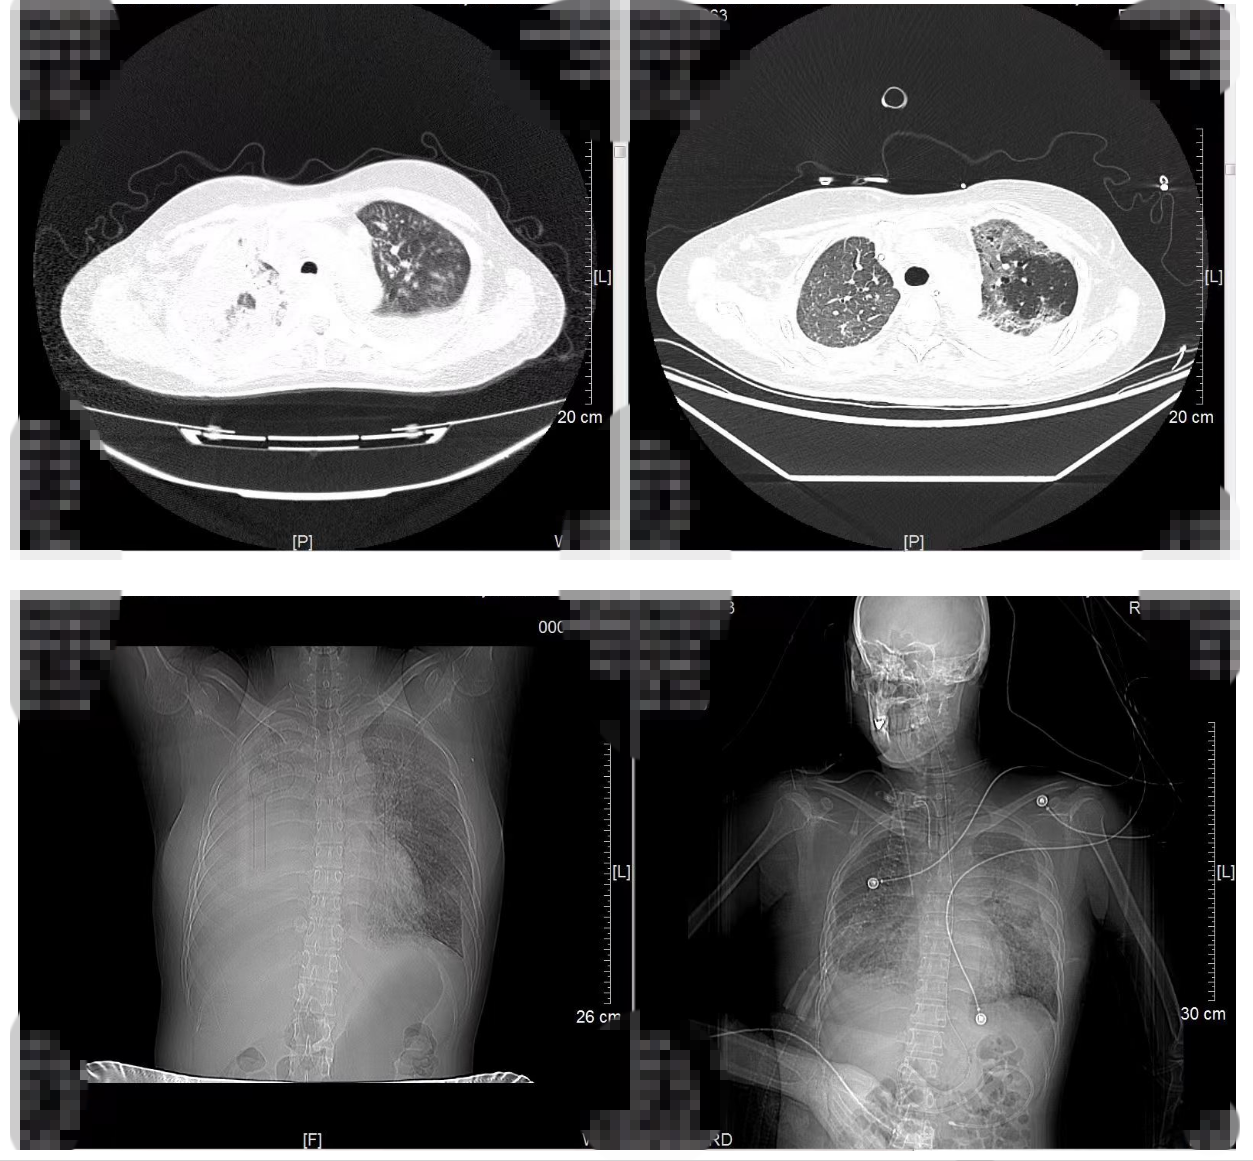

治疗前后肺部影像学对比:左图,治疗前;右图,治疗后

生命支持下的抗肿瘤治疗并非易事。治疗期间章女士出现多脏器功能不全及凝血功能异常,叶勇主任团队为其进行脏器功能保护治疗以保证抗肿瘤治疗顺利进行。经过一个月的靶向治疗,让患者的呼吸功能逐步恢复,部分肿瘤较前退缩。患者恢复清醒,病情好转,已转至普通病房。

经过全院多学科讨论,章女士急需抗肿瘤治疗以控制癌性淋巴管炎。而她的病情并不乐观,呼吸衰竭并伴有持续高热,甚至一度陷入昏迷,在这种情况下,抗肿瘤治疗具有较大风险。根据家属意愿和患者病情,胸部肿瘤内科徐振武主任医师与陈胜佳副主任医师为章女士制定了个体化的靶向抗肿瘤方案。